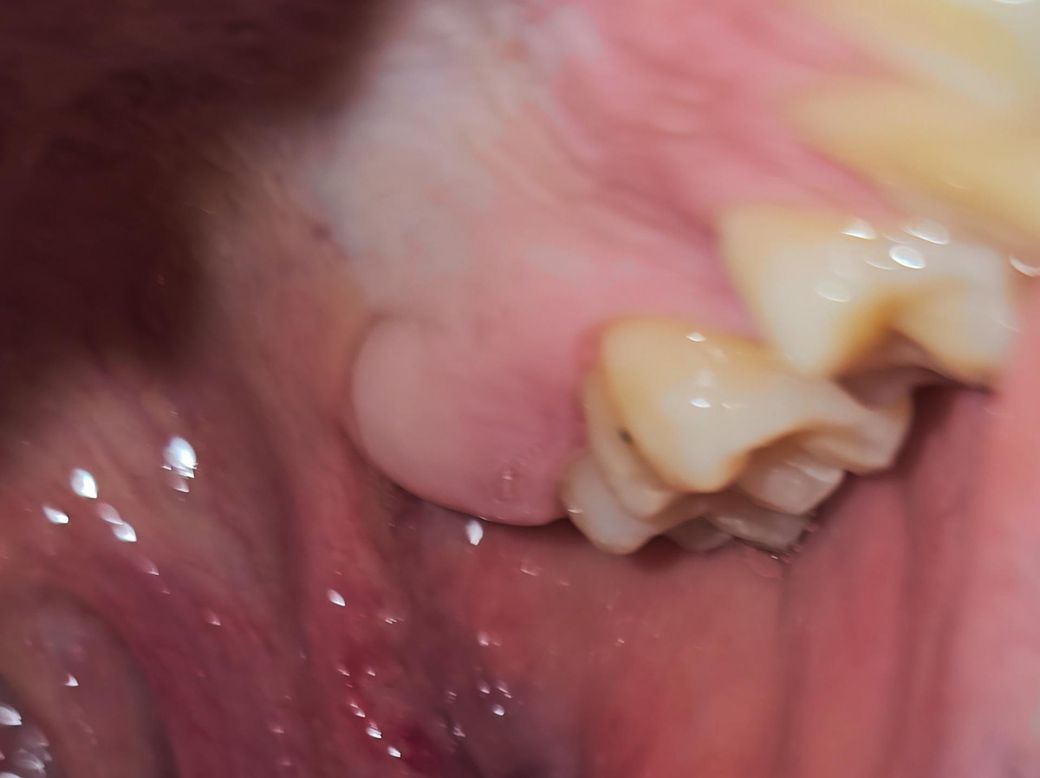

• 1번 째 사진

뭔가 만지면 단단한 느낌이 들기도 합니다.

그리고 구강건조증 있어요. 입천장 봤을때 문제 있어보이나요? 하얀 판 같은 느낌도 들기도 하고 입천장이... 점막 소타액선에 문제 생겨서 침이 안나오는건 아니겠죠? ㅠㅠ